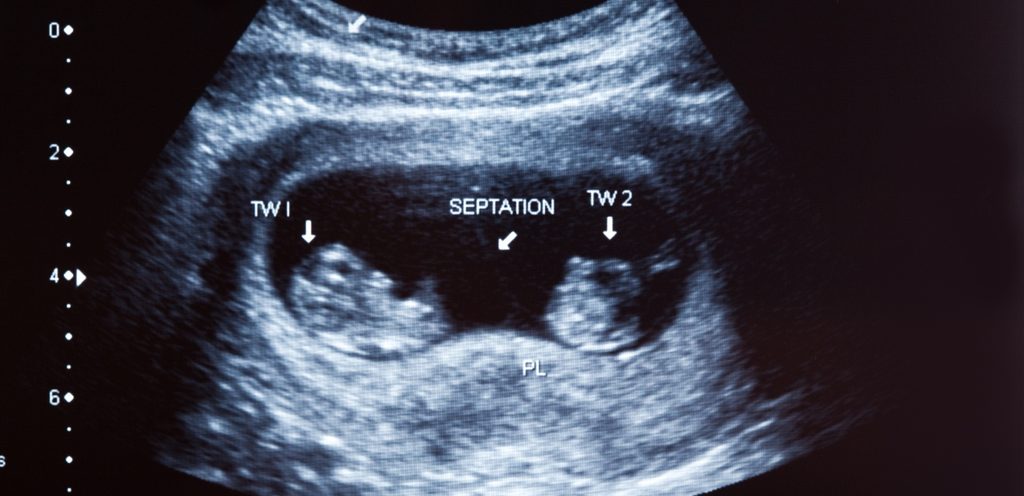

الطريقة الأكثر تأكيدًا للحمل بتوأم هي الموجات فوق الصوتية قبل الولادة. يستخدم هذا الاختبار الموجات الصوتية لإنتاج صور للرحم، كما تتيح الموجات فوق الصوتية معرفة ما إذا كان هناك جنينان أم لا. وهنا اكتشفي كيفية معرفة الحمل بتوأم من الشهر الأول

عندما يقوم اثنان من الحيوانات المنوية بتخصيب بيضتين في دورة واحدة. وينتج عن ذلك مشيمة منفصلة لكل طفل. الحمض النووي للتوأم الأخوي يشبه الحمض النووي للأشقاء من مختلف الأعمار، وقد يكونا من نفس الجنس أو من جنس مختلف.

التوائم المتطابقة

عندما ينقسم جنين واحد من بويضة واحدة وحيوان منوي واحد إلى قسمين. قد يتشارك التوأم في مشيمة واحدة أو يكون لهما مشيمة منفصلة. التوائم المتطابقة تكون دائما من نفس الجنس.